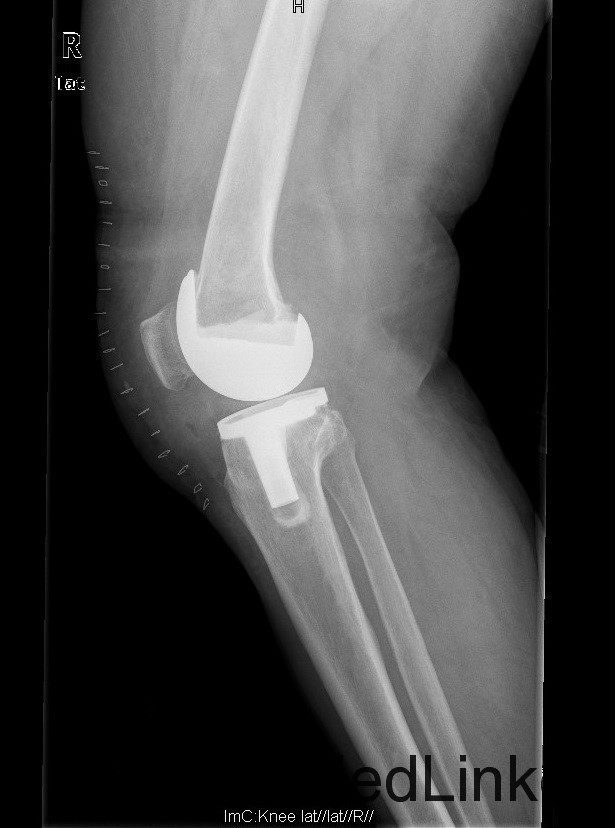

查体:步态跛行,双膝屈曲畸形,左膝外翻、右膝内翻畸形,双膝内外侧关节间隙及髌股关节间隙压痛明显,右侧重,右膝内翻:5°,右膝屈70°,伸-10°;左膝:屈曲:100°,伸:-5°,外翻:20°,双膝主被动屈伸活动时疼痛,双膝髌下摩擦音(+)。 辅助检查:右膝关节间隙狭窄,软骨下骨硬化,髌股关节间隙消失,左膝关节间隙狭窄,软骨下骨硬化,髌股关节间隙狭窄,双膝髌骨、股骨、胫骨周围大量骨赘形成,关节腔内均可见游离体。

诊断:1.双膝重度骨关节炎继发右膝屈曲内翻畸形,左膝屈曲外翻畸形(Krackow Ⅰ型)2.高血压病(3级 极高危) 治疗:积极行术前准备,待血压等稳定后于全麻下行右侧全膝关节置换术,术后常规治疗,并鼓励其锻炼。